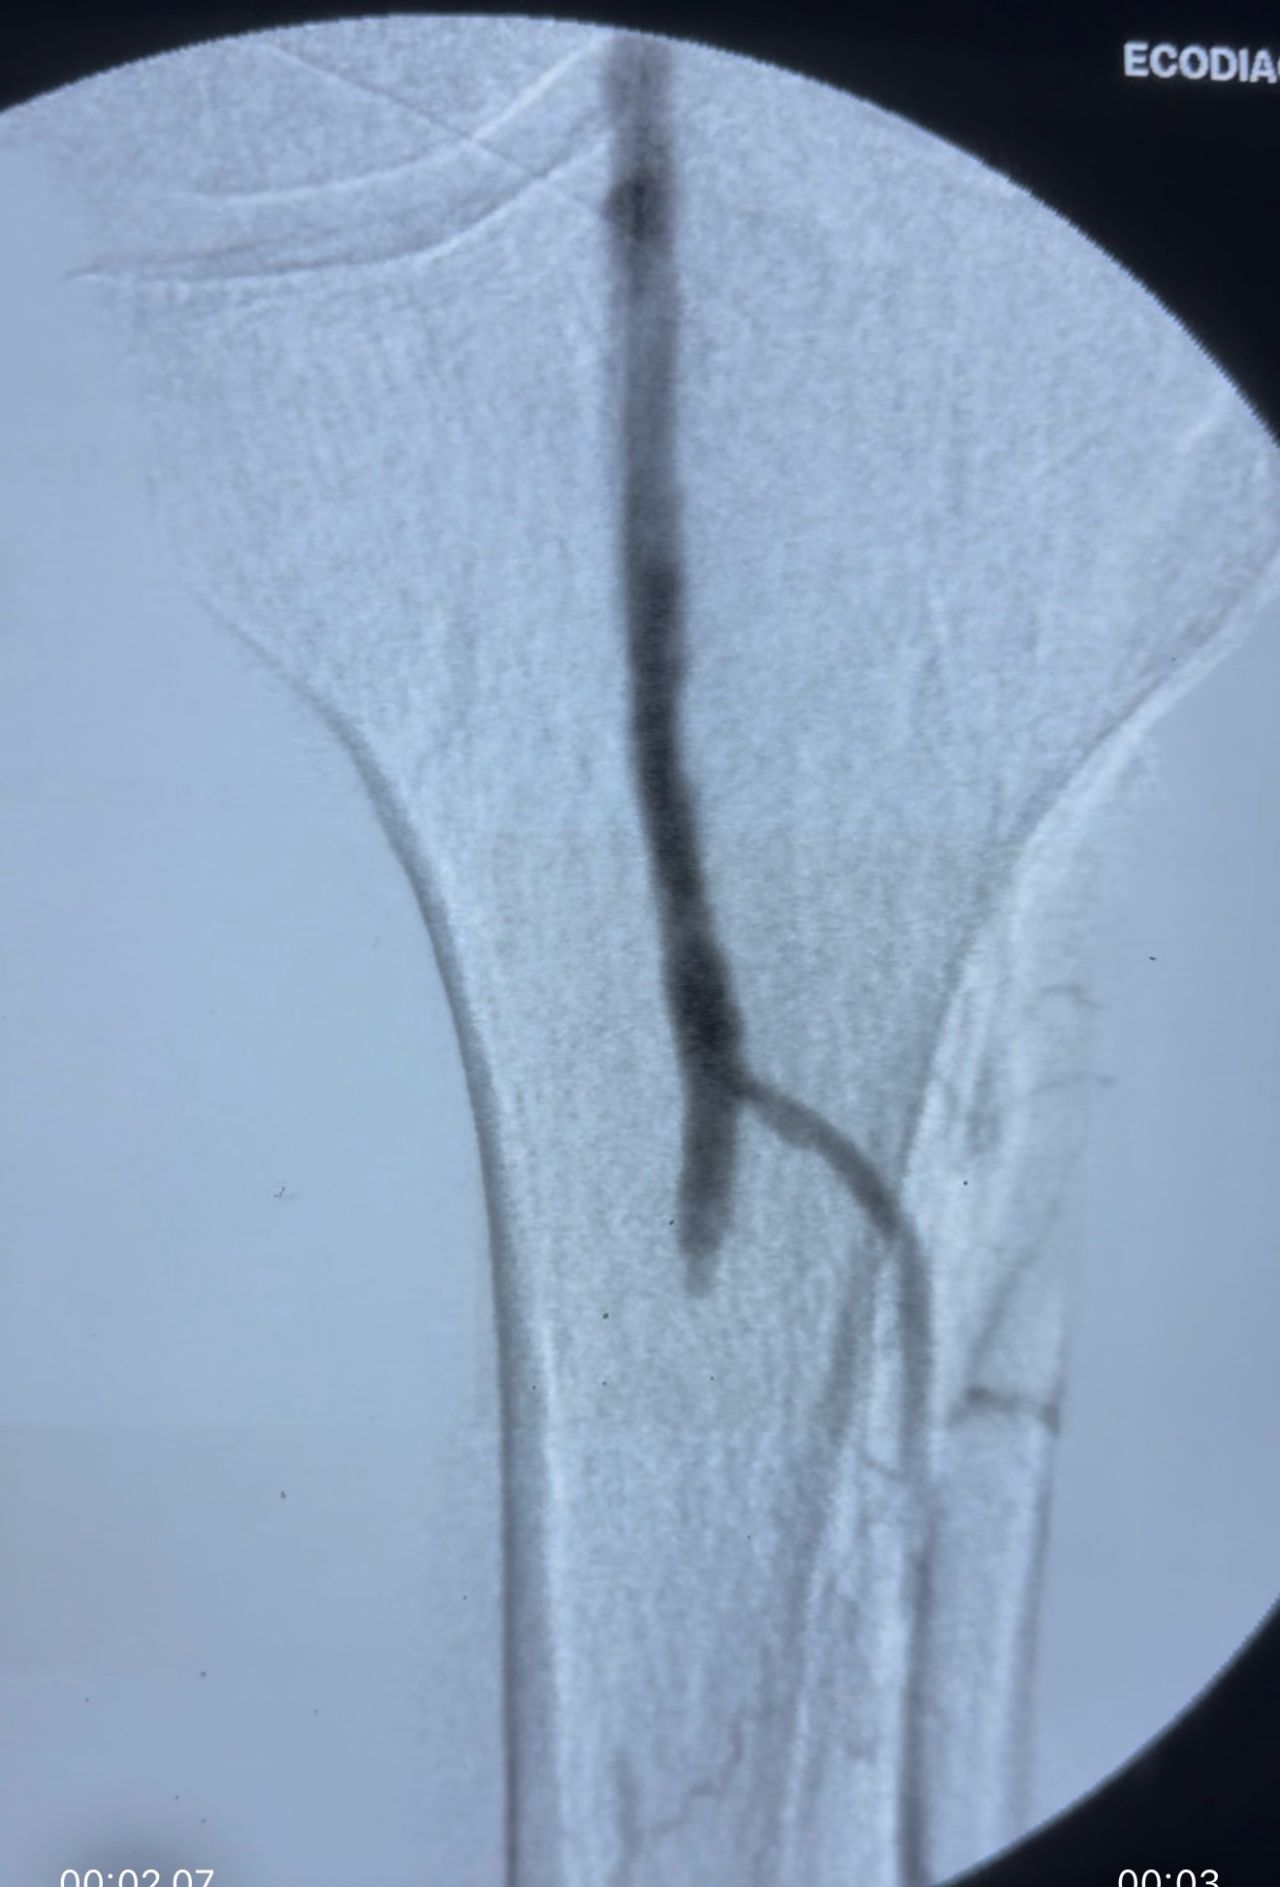

A combined antegrade and retrograde approach was performed. Through the pedal access, multiple atheromatous occlusions were identified in the anterior tibial artery. A balloon was inflated and left in place across the anterior tibial artery arch to protect the distal axis from embolization during thromboaspiration.

Using a manually modified 5F multipurpose catheter connected to a 50 cc syringe, negative-pressure aspiration was performed from the femoral to the popliteal artery, effectively removing extensive thrombotic material.

Final outcome: complete recanalization of the femoral, popliteal, and anterior tibial arteries, with restored distal flow.